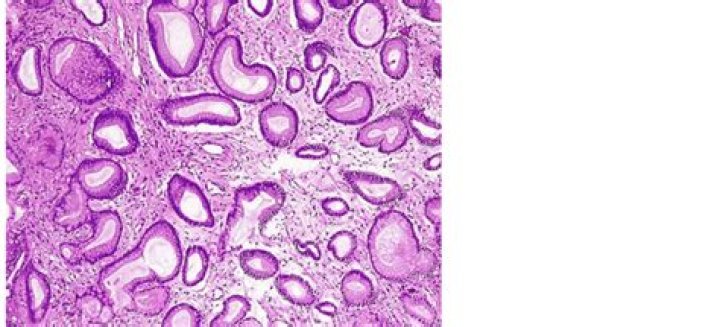

Foveolar hyperplasia was defined as the presence of abnormal branching and twisting and at least a twofold elongation of gastric cardiac foveolae and pits.

Foveolar hyperplasia – Hyperplasia is a word pathologists use to describe an increased number of cells. Foveolar hyperplasia means there is an increased number of foveolar cells on the inside surface of the stomach. The increased number of cells causes the glands to look twisted.

Foveolar hyperplasia is a rare disorder characterized by an overgrowth of mucous cells in the stomach. In children, it may present as a localized lesion that affects the antrum primarily, called focal foveolar hyperplasia (FFH), or as a diffuse lesion, known as Ménétrier disease.